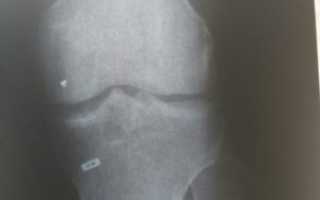

При рентгенографическом исследовании выявляются только хотя бы частично кальцифицированные свободные тела. Свободные тела, полностью состоящие из хряща, встречаются наиболее часто и совершенно неразличимы на рентгенограммах.

Во всех случаях необходимо выполнить рентгенографию в двух проекциях. Для чёткой оценки межмыщелковой вырезки рекомендовано исследование в проекции Розенберга (переднезадняя проекция в положении сгибания в коленном суставе на 45°).

- Рентгенограмму коленной области;

- Компьютерную томограмму.

Они наглядно демонстрируют дополнительное плотное образование, не связанное с какими-либо суставными структурами. Если это образование не выявляется во время рентгенограммы, выполняют снимок с контрастированием воздухом (пневмоартрография) или двойным контрастированием (контрастное вещество и воздух).